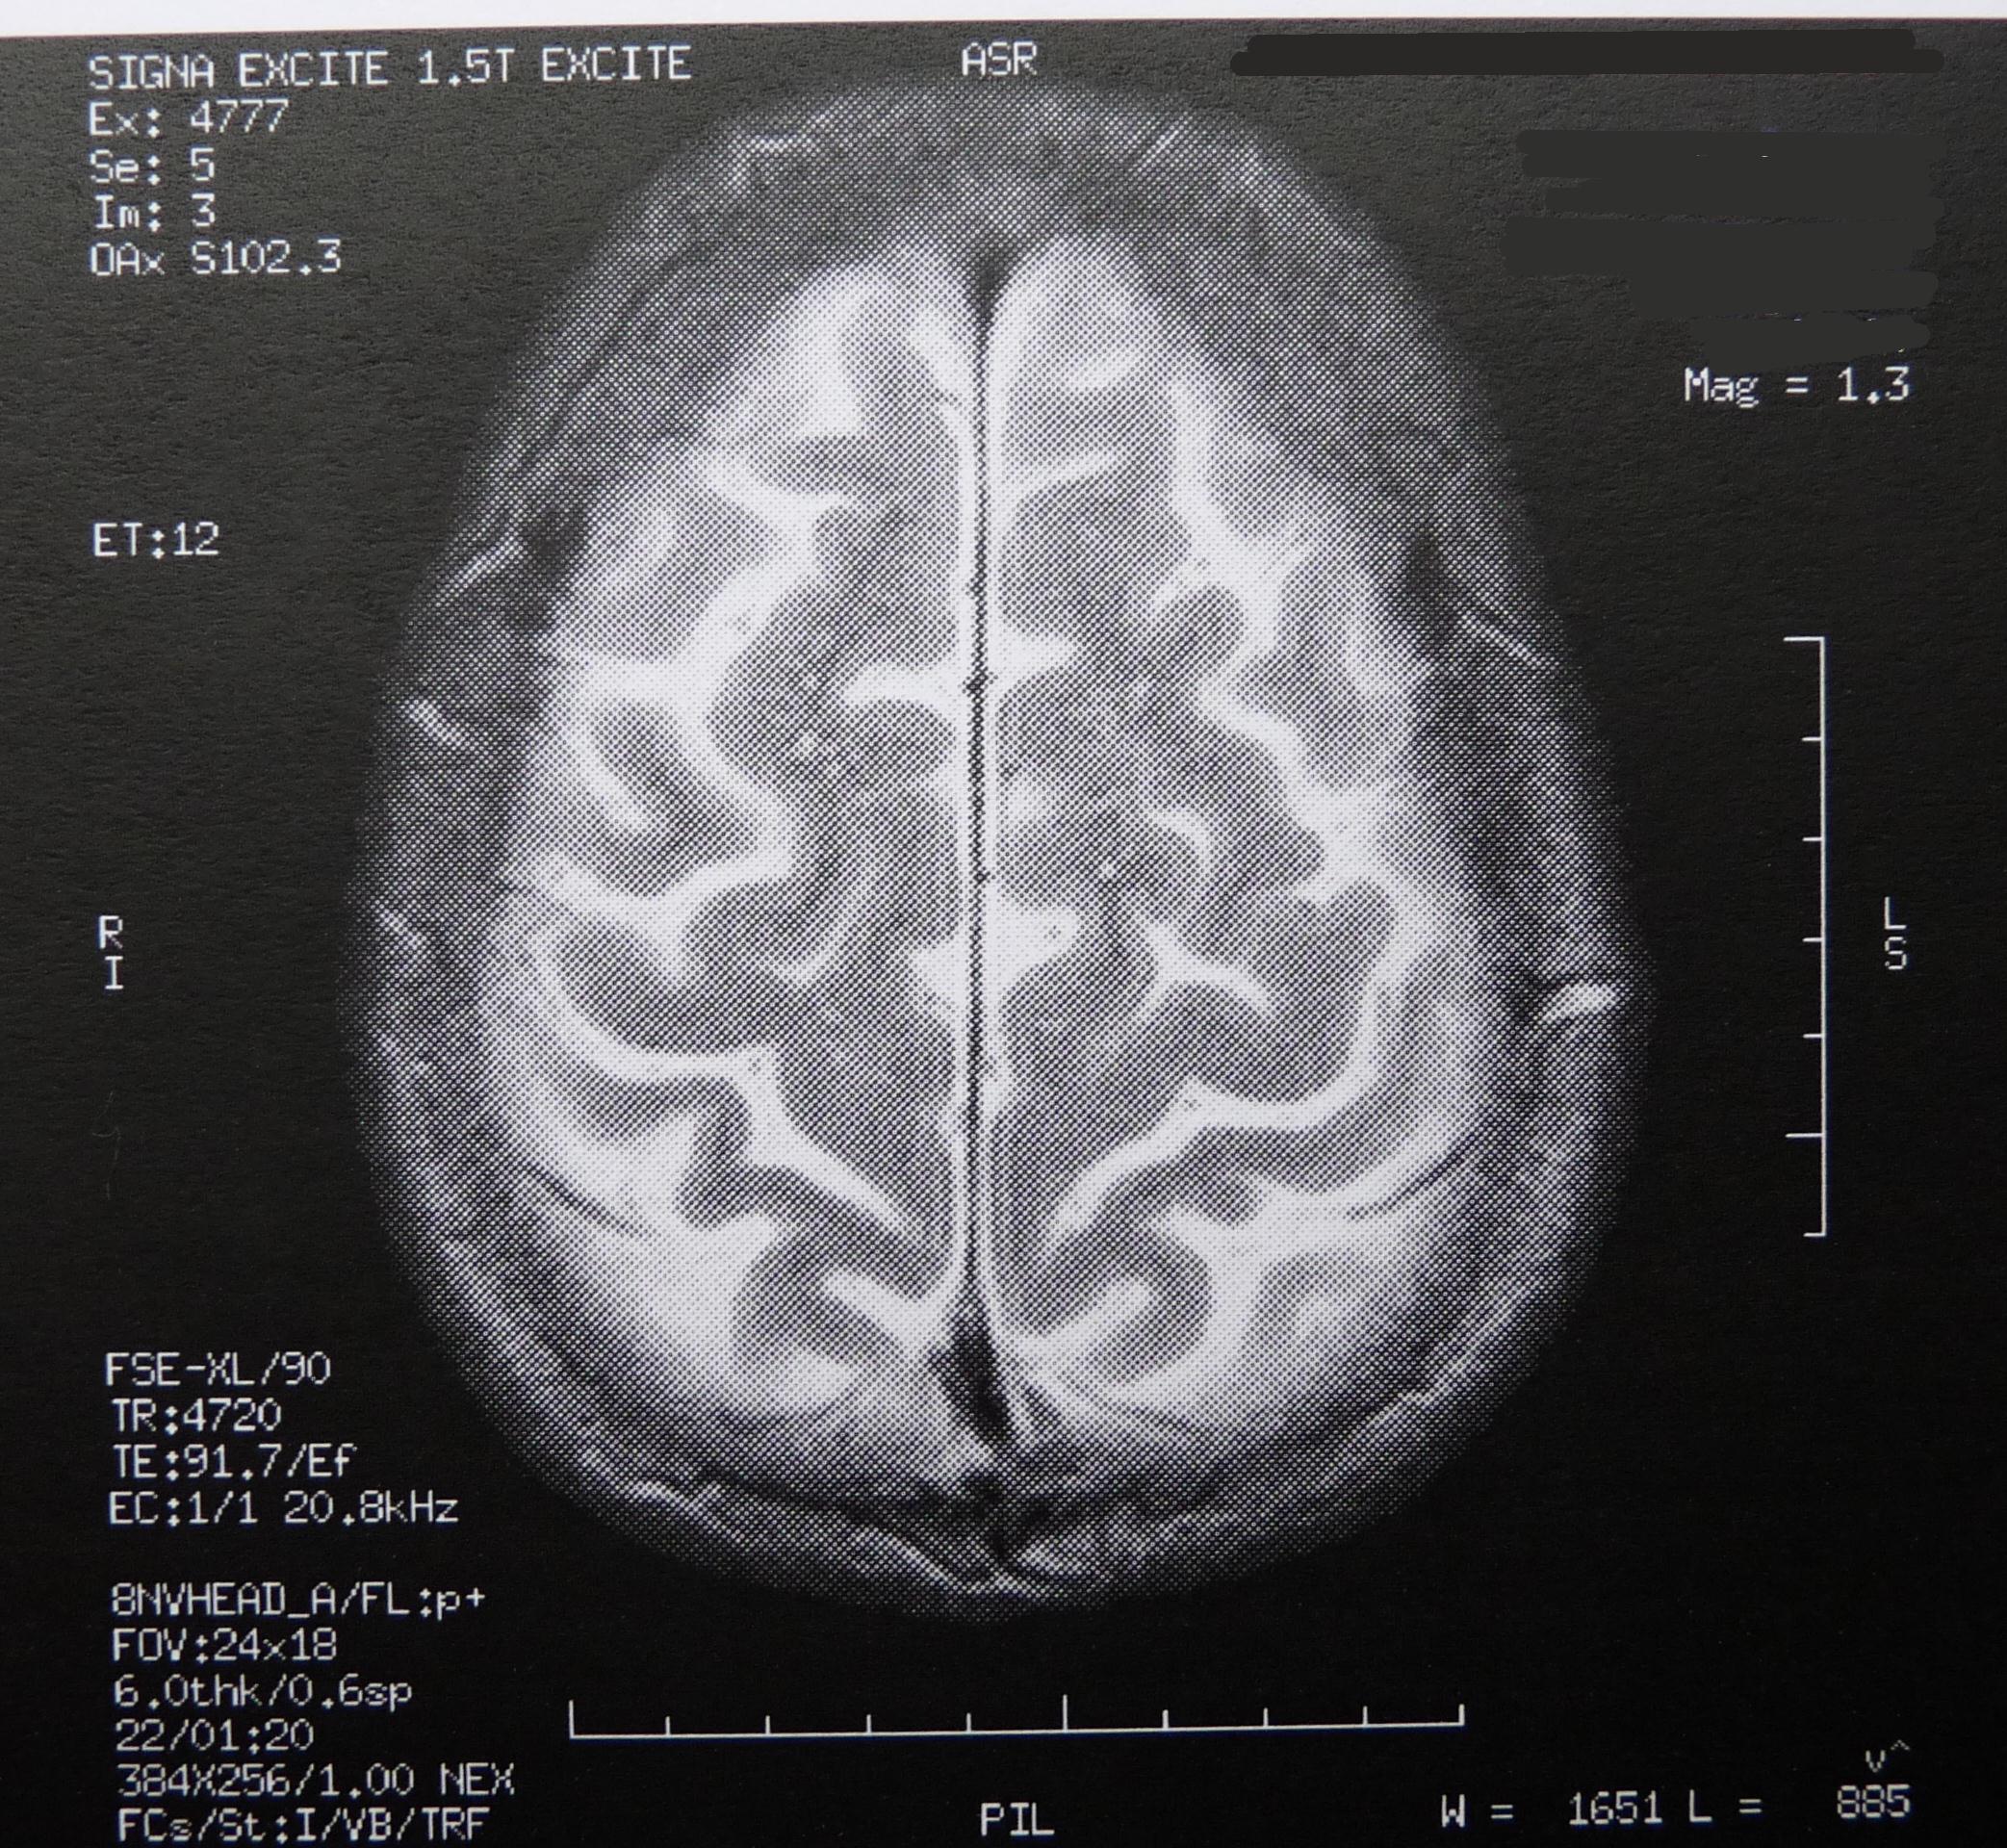

Ein Team um Jakob Kaminski und Andreas Heinz von der Berliner Charité hat in einer Studie Intelligenztests von fast 1500 Jugendlichen mit den epigenetischen Veränderungen des Gehirns der Probanden verglichen. Für die Studie wurden jene Gene untersucht, die im Nervensystem für die Signalübertragung mit dem Botenstoff Dopamin von Bedeutung sind. Dopamin spielt eine wichtige Rolle im Belohnungssystem des Gehirns. Es steuert maßgeblich den Antrieb und die Motivation einer Person.

Die Forscher konnten in ihrer Studie zeigen, dass die epigenetische Regulation der Signalübertragung mit Dopamin und die individuelle Leistung in Intelligenztests zusammenhängen. Durch die Veränderung am Dopamin-Rezeptorgen wird das Signalübertragungssystem von der Zelle stummgeschaltet. Als Folge werden weniger Dopamin-Rezeptoren auf den Nervenzellen gebildet und die Signalübertragung wird verringert. In der aktuellen Studie ging diese Stummschaltung des Gens mit schlechteren Ergebnissen in den Intelligenztests einher.